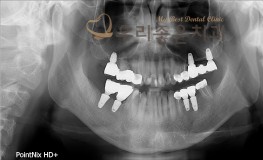

우리좋은치과 치아 상실 및 골소실 → 뼈이식 및 임플란트 보철 치료(임**2016...

No.296

임플란트

2019-05-31

1391